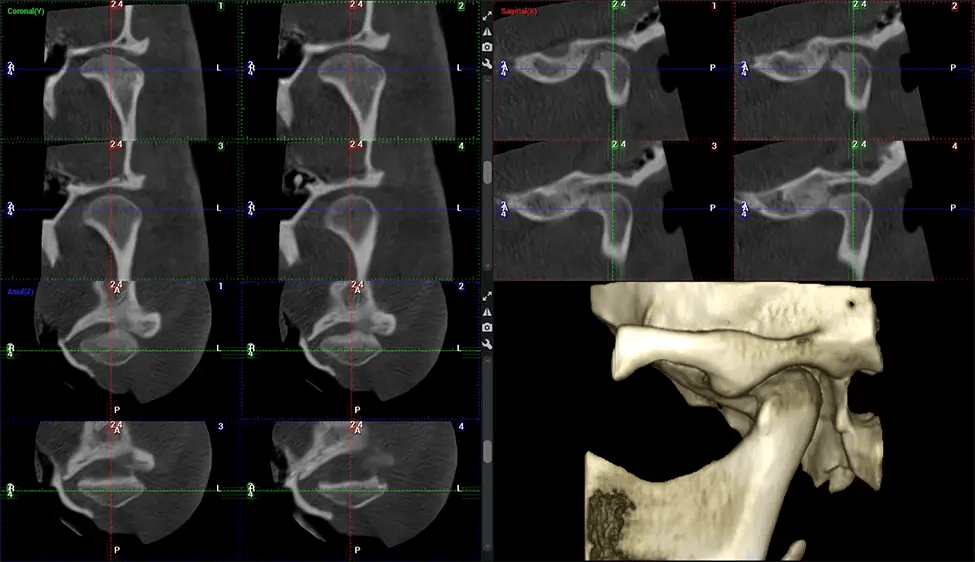

Planmeca Viso G7 CBCT ( Cone Beam CT Scan ) is designed to surpass the demands of industry leaders, specialists, and large institutions. It’s has a large ø25×30 cm sensor with four built-in cameras. It can capture unlimited volume sizes from a ø3×3 cm to a ø30x30cm volume capturing the skullcap through C7 on the cervical spine. The Planmeca Viso G7 offers the industry’s largest single volume scan of ø30×19 cm. It’s poised to handle advanced imaging modalities such as Planmeca ProFace® and Planmeca 4D™ Jaw Motion technology. The occipital head support allows an unimpeded view of facial tissue.

After the scanning process, the captured X-ray images are processed by the CBCT software, which applies algorithms to reconstruct a detailed 3D image of the scanned area. The software compiles these individual X-ray images and creates a digital 3D representation of the patient’s anatomy. The reconstructed 3D CBCT image can be viewed and analyzed by the dentist or radiologist. This image can be manipulated, rotated, and zoomed in or out to examine specific structures and evaluate the patient’s condition.